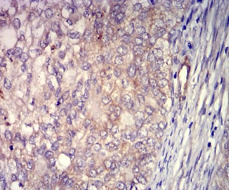

IHC    1/200 - 1/1000